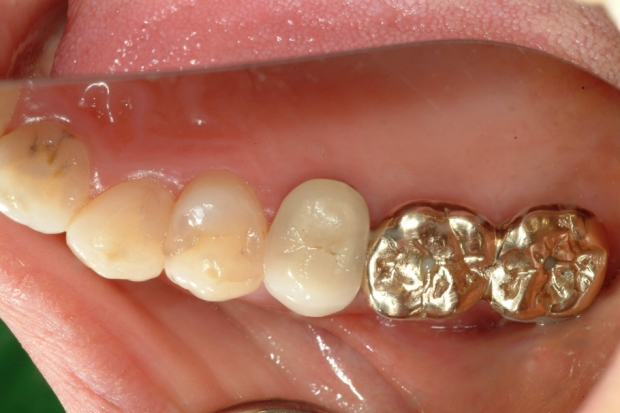

牙冠粘接修复